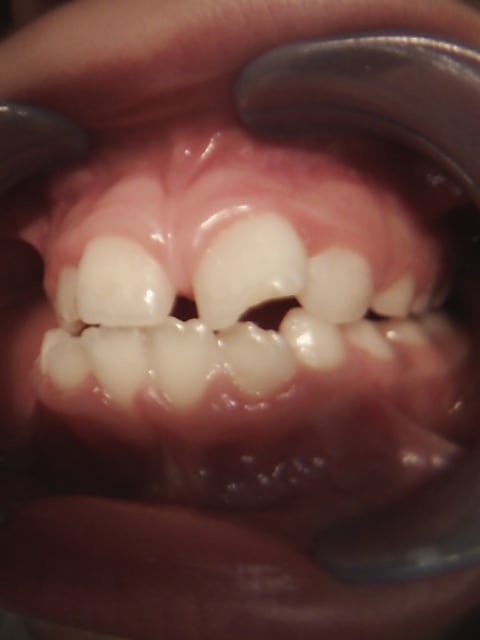

- Enfant de 6 et demi ans,

- Choc suite chute en vélo il y a environ 6 mois

- Visiblement ce qui a alerté les patients c'est la position de la dent ..

- Percussion négative mais pas (?) ou peu de réaction aux tests thermiques

Si aujourd'hui la dent est en malposition c'est sans doute à cause de l'interposition de la lèvre inférieure. Le centre de résistance de la 21 étant positionné plus coronairement, la 21 offre moins de résistance à la version corono-vestibulaire que la 11, d'où l'asymétrie avec 11.

Il y a aussi un problème d'articulé inversé à droite, non?